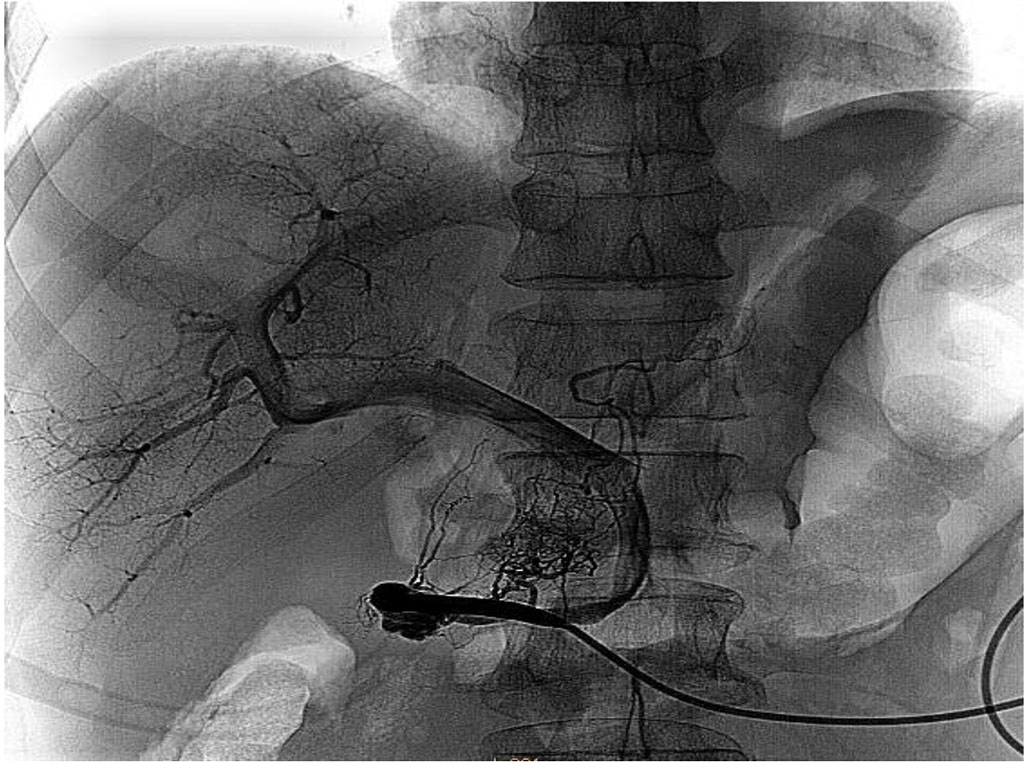

After that, it was flushed with a heparin solution (2500 units per 80 ml of physiological solution), and an obturator line was inserted into the lumen. After catheterization, portography was performed using a Phillips Allure FD 20 angiographic unit. The intravascular position of the catheter in the portal system was assessed, followed by measurement of invasive pressure. Fig. 2.

Figure 2 Control portography. The architecture of the portal system is visualized.